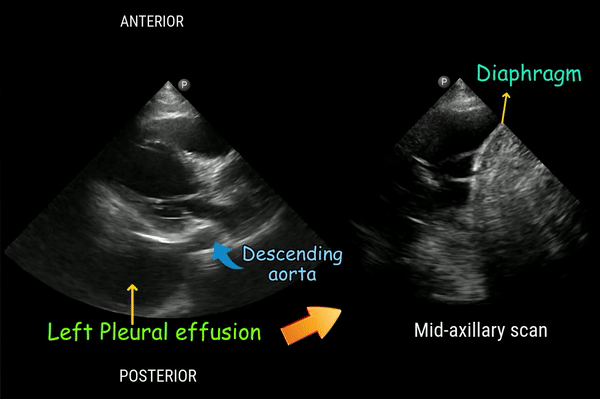

Below is an example of a left pleural effusion in a patient with malignancy, which can easily be mistaken for a pericardial effusion during a quick bedside exam. I obtained this image using a handheld device while the patient was in the dialysis chair, where the optimal positioning of both the physician and patient may not always be possible. Pay close attention to the position of the descending aorta. Scanning from different angles helps with clarity. Also, notice the fibrin stranding in the mid-axillary view, which is indicative of an exudative pleural effusion.